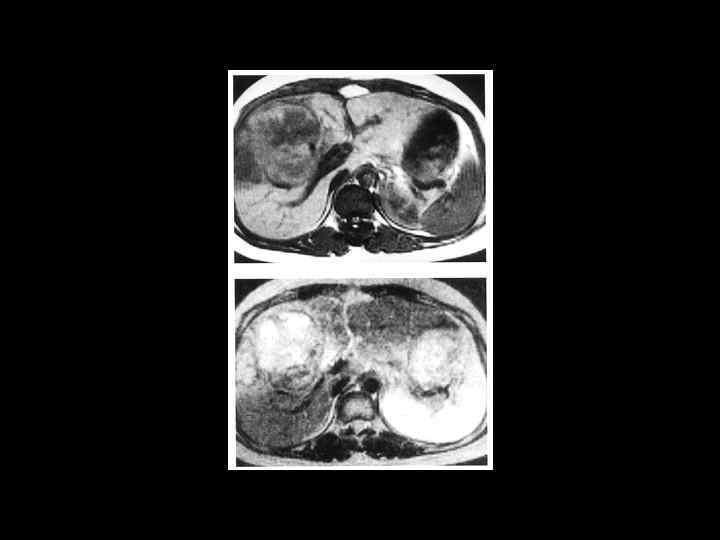

АКТУАЛЬНЫЕ ВОПРОСЫ РЕНТГЕНОЛОГИИ ЛУЧЕВАЯ ДИАГНОСТИКА ОЧАГОВЫХ ПОРАЖЕНИЙ ПЕЧЕНИ Кавернозная гемангиома печени МР- семиотика: - образование с гиперинтенсивным сигналом на Т-2 взвешенном изображении -после введения контрастного вещества- динамика изменений такая же, как при КТ

АКТУАЛЬНЫЕ ВОПРОСЫ РЕНТГЕНОЛОГИИ ЛУЧЕВАЯ ДИАГНОСТИКА ОЧАГОВЫХ ПОРАЖЕНИЙ ПЕЧЕНИ КИСТЫ ПЕЧЕНИ МР семиотика: - образования с гиперинтенсивным сигналом, четкими, ровными контурами

АКТУАЛЬНЫЕ ВОПРОСЫ РЕНТГЕНОЛОГИИ ЛУЧЕВАЯ ДИАГНОСТИКА ОЧАГОВЫХ ПОРАЖЕНИЙ ПЕЧЕНИ ЭХИНОКОККОВЫЕ КИСТЫ УЗИ: краевые кольцевидные обызвествления КТ: низкоплотностные образования с перегородками и четкими контурами МРТ: образования дающие гиперинтенсивный сигнал на Т 2 взвешенных изображениях